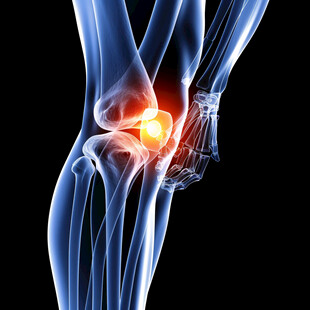

膝关节X光检查 商用作品

膝关节X光检查 商用作品 -

膝关节X光检查 商用作品

膝关节X光检查 商用作品 -

人体膝关节疼痛的医学图解 商用作品

人体膝关节疼痛的医学图解 商用作品 -

人体膝关节3D解剖图 商用作品

人体膝关节3D解剖图 商用作品 -

膝关节X光检查 商用作品

膝关节X光检查 商用作品 -